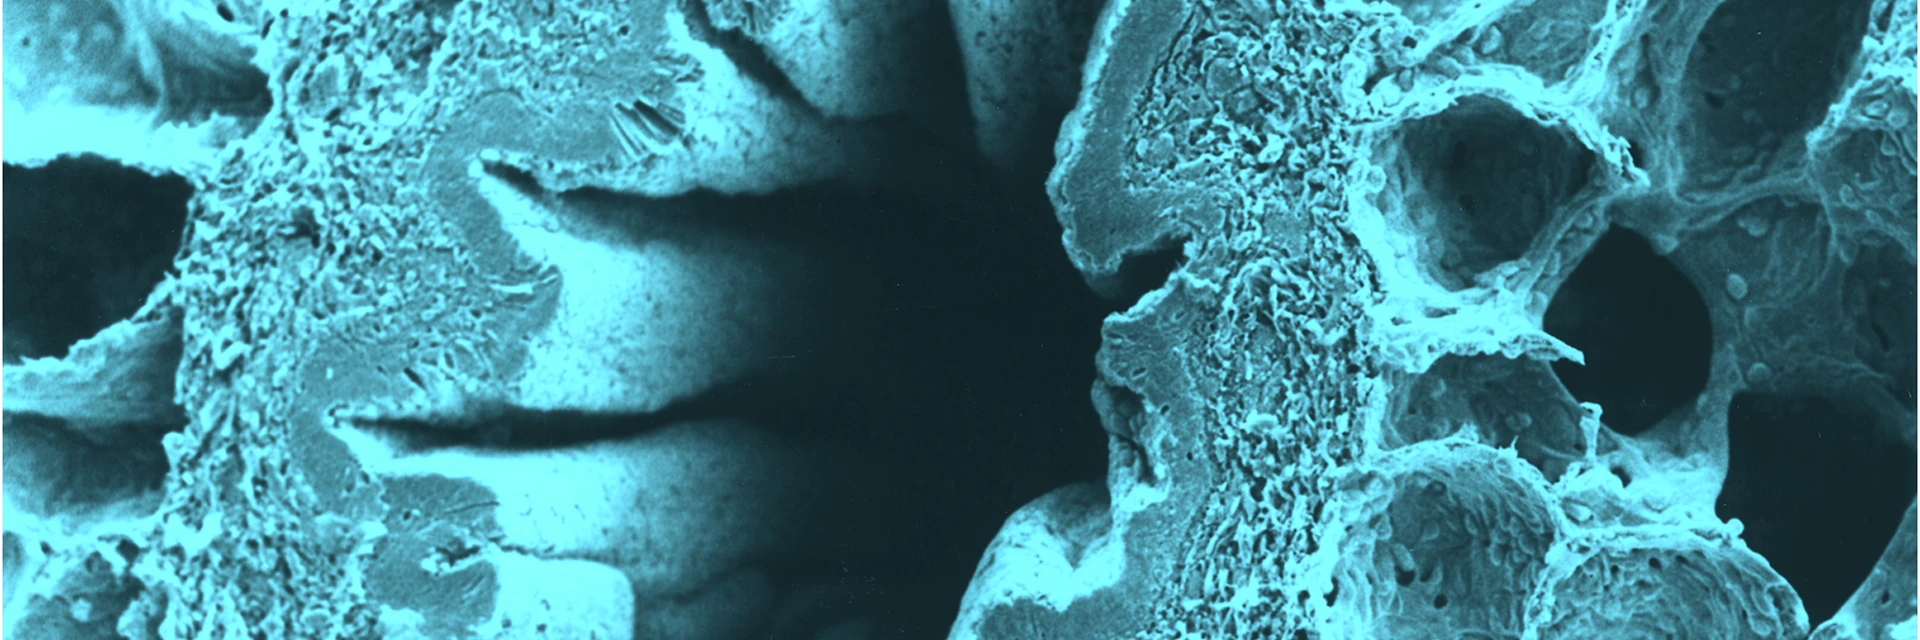

Human lung tissue under microscope view.